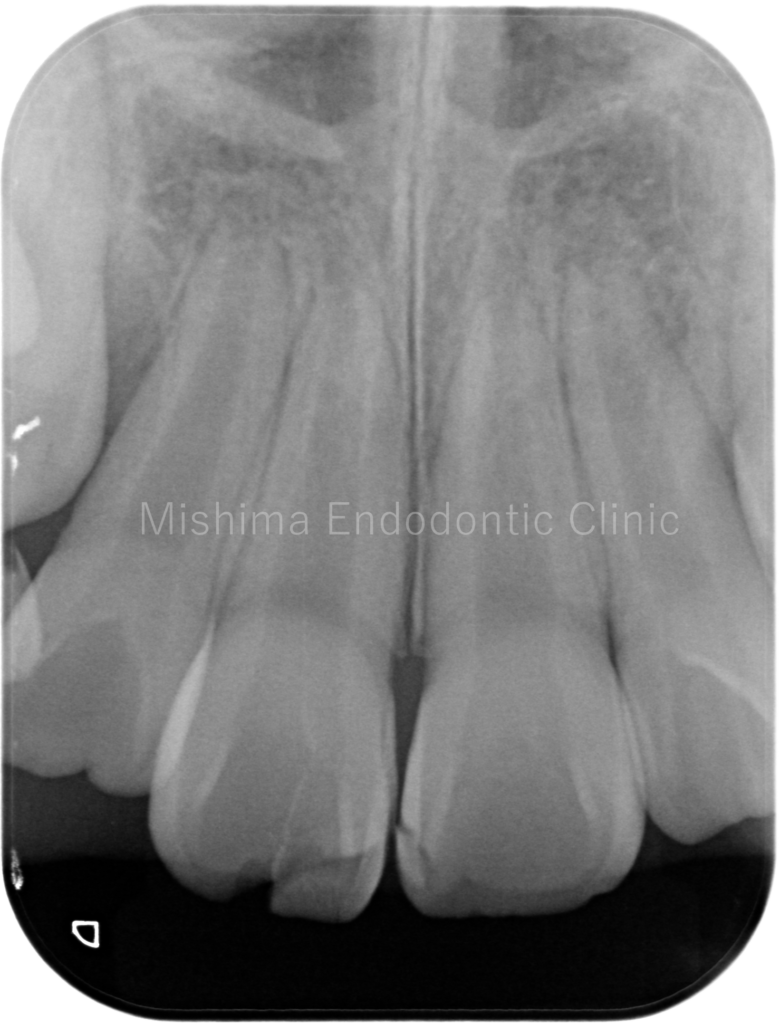

After

術直後